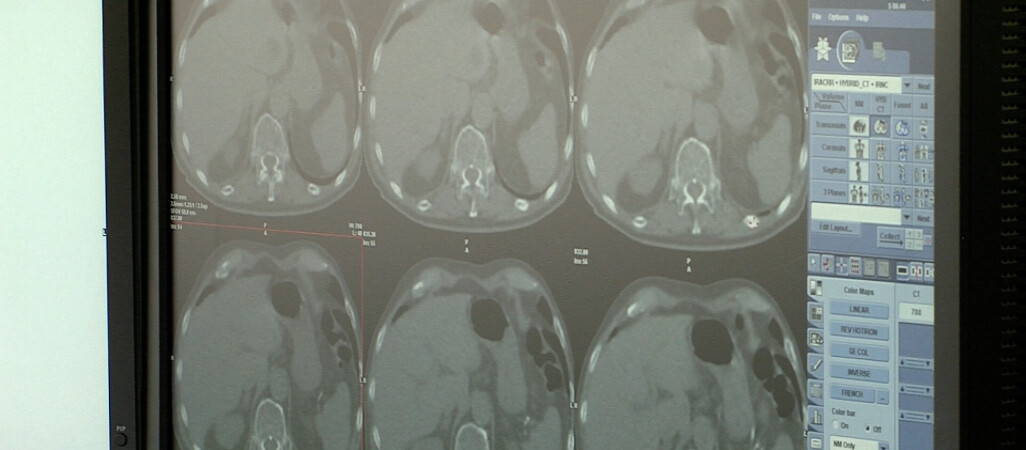

– Mamy teraz oręża walki z udarem mózgu, jeżeli już do niego dojdzie. Mamy dwa rodzaje leczenia, jeżeli chodzi o udar niedokrwienny to tzw. leczenie trombolityczne, którego ideą jest rozpuszczanie skrzepliny – tłumaczy dr n. med. Małgorzata Wiszniewska, neurolog.

Druga metoda to operacyjne usunięcie skrzepliny z żyły. Później zostaje walka z ewentualnymi następstwami choroby. Dzieci mogą mieć trudności w nauce, cierpieć na napady padaczkowe, a nawet nawroty udarów. Jednak rokowania u dzieci są znacznie lepsze niż u dorosłych.